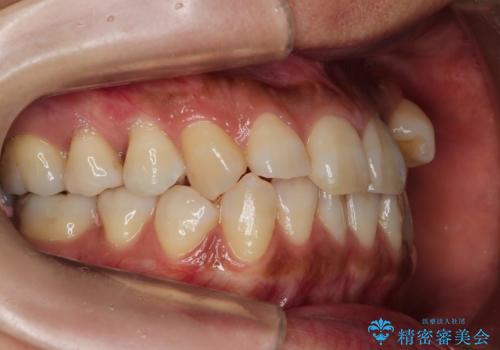

ハーフリンガル抜歯矯正 八重歯を改善する

- 小臼歯4本抜歯によるハーフリンガル・ワイヤー矯正を計画した。

シビアな八重歯がきれいに歯列にはいることにより、笑った時の印象などもかなり大きく変わります。